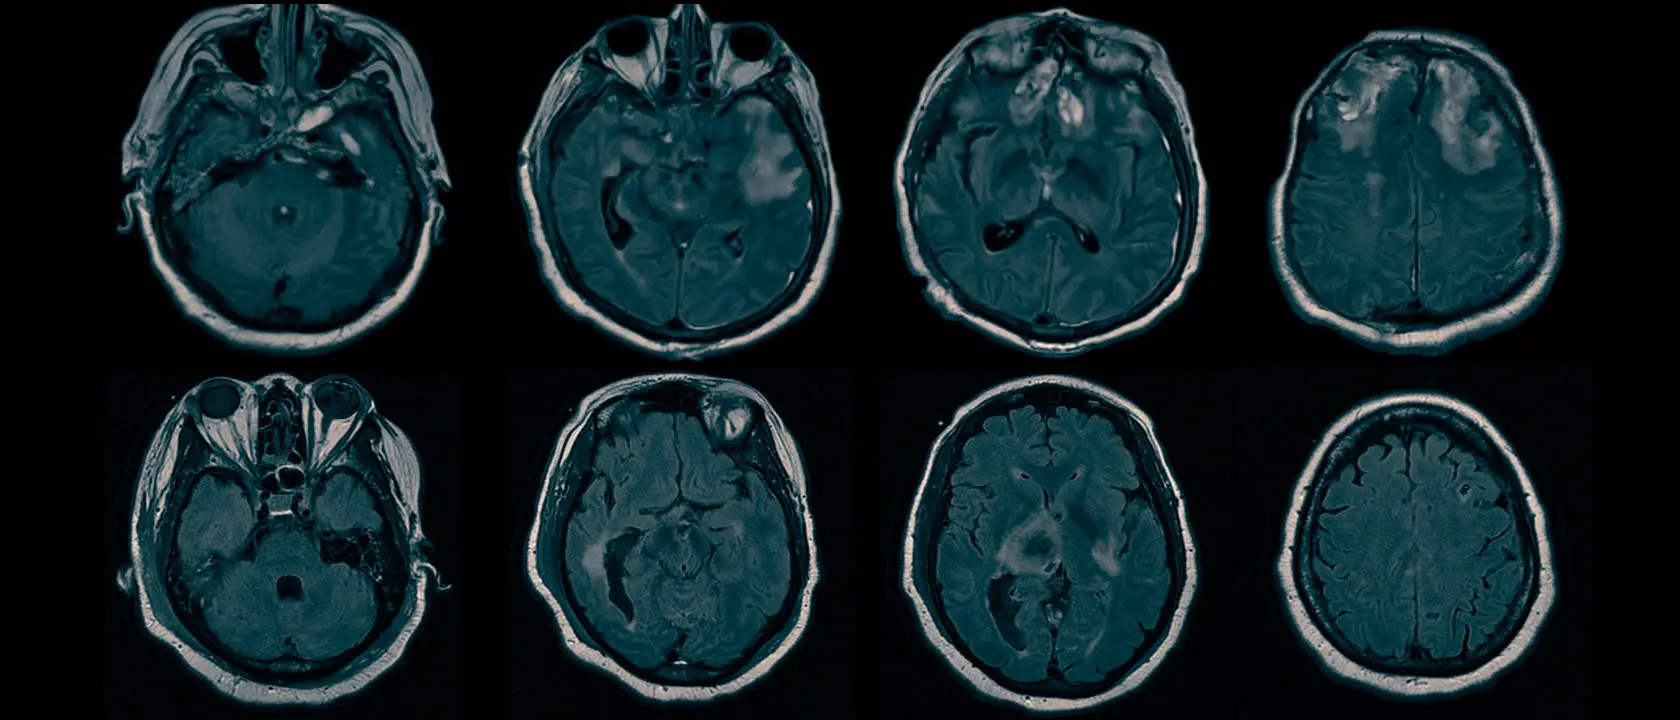

Scientists from Columbia University have identified brain injuries that may be responsible for hidden consciousness in patients with brain damage. Hidden consciousness, also known as cognitive motor dissociation (CMD), occurs when individuals with brain injuries appear unconscious but retain some degree of awareness. Using EEG and structural MRI scans, the researchers found that patients with CMD had intact brain structures related to arousal and command comprehension, suggesting that they could hear and understand verbal commands but were unable to carry them out due to disruptions in brain circuits responsible for relaying instructions to the muscles. These findings could help identify brain-injured patients with hidden consciousness and improve predictions of recovery with rehabilitation. Further research is needed before these approaches can be applied in clinical practice.